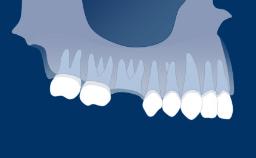

When indicated for missing teeth, dental implants are a means to fulfill these requirements.

This Learning Module will outline the implant design features and characteristics that are aimed at facilitating integration with the hard and soft tissues, allowing them to serve as anchorage elements for prosthetic reconstructions whilst also withstanding occlusal loading forces.